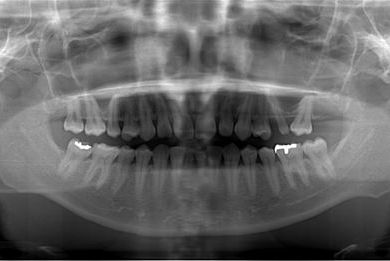

| 性別/年齢 | 女性 / 28歳 | ||||||||||||||||||||||||||||||||

| 主訴 | 下前歯の色が気になるので、ホワイトニングかセラミック治療できれいにしたい。(下前歯2本は乳歯でした) | ||||||||||||||||||||||||||||||||

| 治療方針 | 下顎前歯、乳歯を抜歯し、セラミック治療にて審美的回復を行う。 | ||||||||||||||||||||||||||||||||

| 治療内容 | エンプレスジルコニアフレームオールセラミッククラウンブリッジ4本 | ||||||||||||||||||||||||||||||||

| 総治療費 | 723,450円 | ||||||||||||||||||||||||||||||||

| 治療期間 | 2ヶ月 |